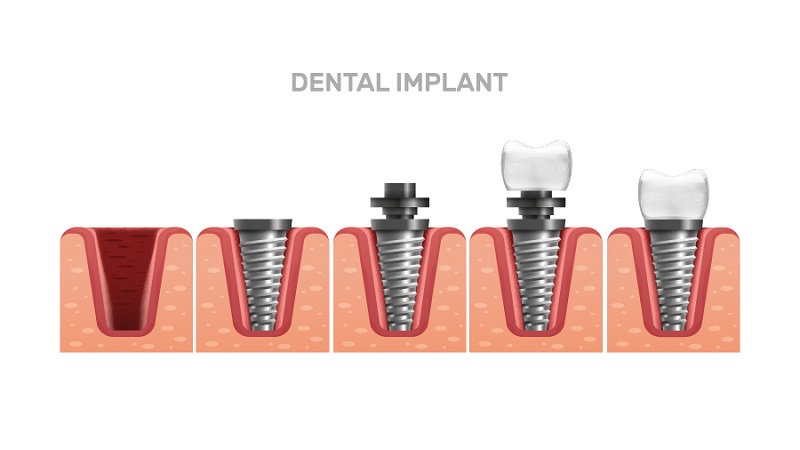

- ایمپلنت دندان اصفهان